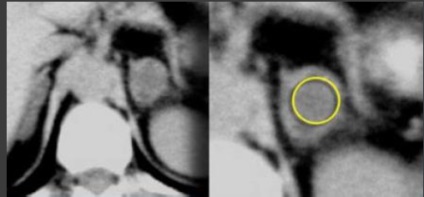

MR modificări de schimbare chimică utilizează frecvențe diferite precesional de protoni în apă față de protoni grăsime din cadrul aceluiași voxel și creează în fază și în afara faze de imagine în care un semnal de protoni sunt însumate sau scăzute unul de altul. Această secvență evaluează grăsime intracitoplasmatică găsite în cele mai multe adenoamelor. Cele mai multe adenoame arată o scădere a intensității semnalului în imagini de fază distincte.

MR. T1VI hiperplazie sau adenom.